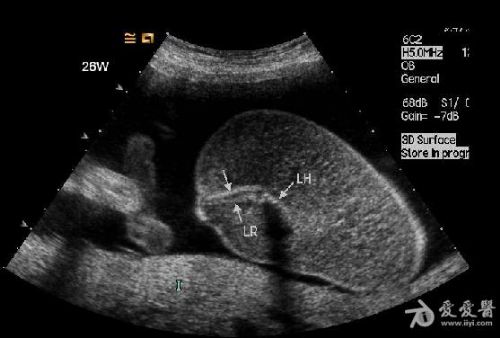

5、无心畸胎常有广泛的皮下水肿声像改变,在上部身体常有明显的水囊瘤。

3.无心畸胎在一月之内胎体增长迅速,明显超过正常胎儿,并伴发颈部水囊瘤及全身皮肤高度水肿。